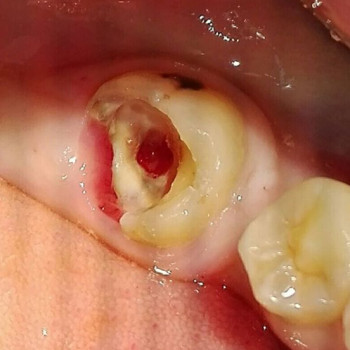

Лечение зубных каналов в Запорожье - Страница 3